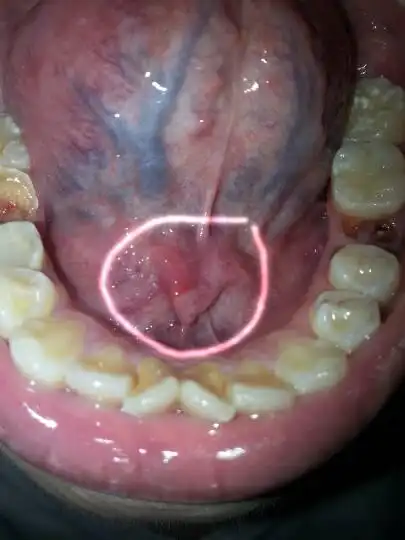

我舌头下面长了一个东西,请问这是什么,应